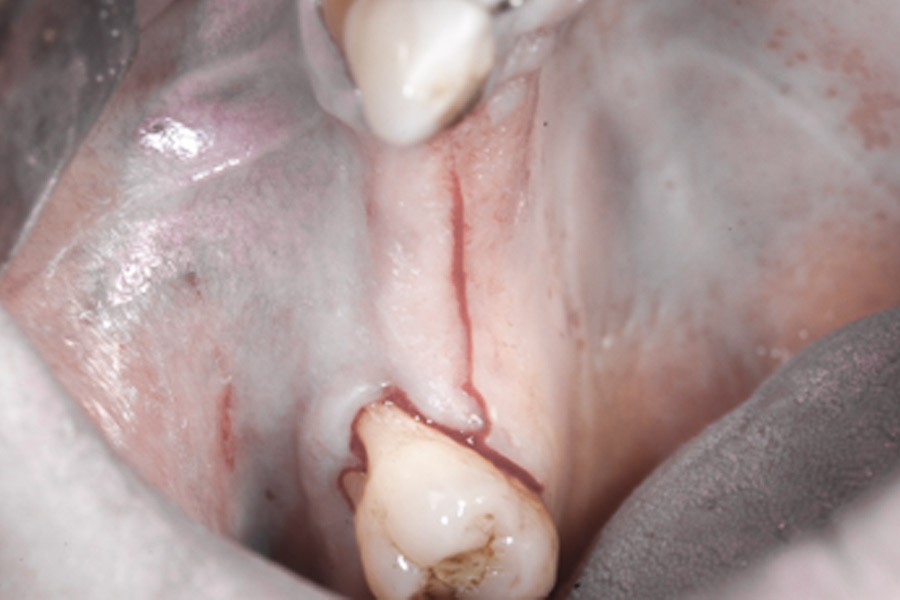

Zabieg odbudowy zębodołu powinno się wykonać możliwe jak najszybciej po usunięciu zęba. Jego celem jest odbudowa naturalnej objętości kości w miejscu utraconego zęba, a następnie szybkie wprowadzenie implantu. Najlepsze rezultaty uzyskuje się przy zastosowaniu biomateriału w formie bloczków kolagenowych lub granulatu, które dają trwałe efekty odbudowy oraz optymalną funkcję i estetykę odtworzonych koron zębów na wszczepionym implancie.

Bloki kolagenowe używane są najczęściej do odbudowy geometrycznych, trójwymiarowych ubytków kostnych, których doskonałym przykładem jest zębodół po ekstrakcji zęba. Jest to jeden ze sposobów na procedurę „socket preservation”, czyli natychmiastową lub wczesną odbudowę zębodołów poekstrakcyjnych dla osiągnięcia optymalnych efektów estetycznej odbudowy protetycznej koron zębów na implantach.